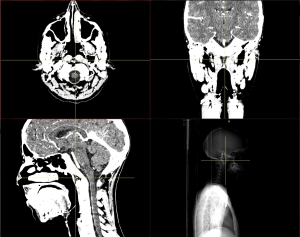

Volumes acquired for medical examination purposes are constantly increasing in size. For this reason, the computer’s memory is the limiting factor for visualizing the data. Bricking is a well-known concept used for rendering large data sets. The volume data is subdivided into smaller blocks to achieve better memory utilization. Until now, the vast majority of medical workstations use a linear volume layout. We implemented a bricked volume layout for such a workstation based on Java as required by our collaborative company partner to evaluate different common access patterns to the volume data. For rendering, we were mainly interested to see how the performance will differ from the traditional linear volume layout if we generate images of arbitrarily oriented slices via Multi-Planar Reformatting (MPR). Furthermore, we tested access patterns which are crucial for segmentation issues like a random access to data values and a simulated region growing. Our goal was to find out if it makes sense to change the volume layout of the medical workstation to benefit of bricking. We were also interested to identify the tasks where problems might occur if bricking is applied. Overall, our results show that it is feasible to use a bricked volume layout.Additional Files and Images